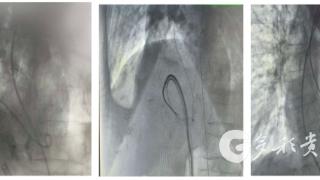

遵义市中医院成功开展高龄心梗后室间隔穿孔介入封堵术

来源:多彩贵州网多彩贵州网讯 近日,遵义市中医院心血管内科成功为一名78岁高龄女性患者实施心梗后室间隔穿孔介入封堵术。此次手术的顺利完成,是该院继左心耳封堵、卵圆孔未闭封堵、先天性心脏病介入治疗后,在结构性心脏病介入治疗领域取得的又一重要进…